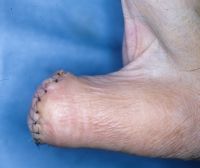

Case 2

This elderly gentleman presented with an enlaging

tumor of his thumb tip. He did not know how long

it had been present. He complained that it bled

frequently, was unstable, and he requested an

amputation. He had no lymphadenopathy or evidence of

metastatic disease on chest Xray. |

| Plain films showed

loss of the distal 2/3 of the distal phalanx. |

| Excisional biopsy

in the form of an interphalangeal disarticulation: |